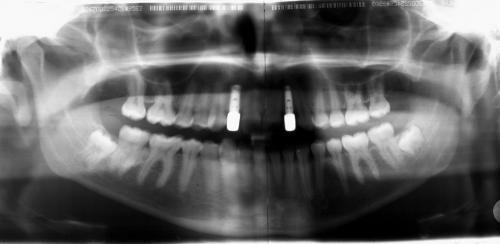

Röntgenbefund

Vor Entfernen der festen Zahnspange mußte sichergestellt sein, daß die Lücken für die Zahnimplantate ausreichend breit und auch die Wurzeln der die Lücke begrenzenden Zähne ausreichend parallel waren (linkes Bild). Rechts die Situation nach Einsetzen der endgültigen Versorgung.